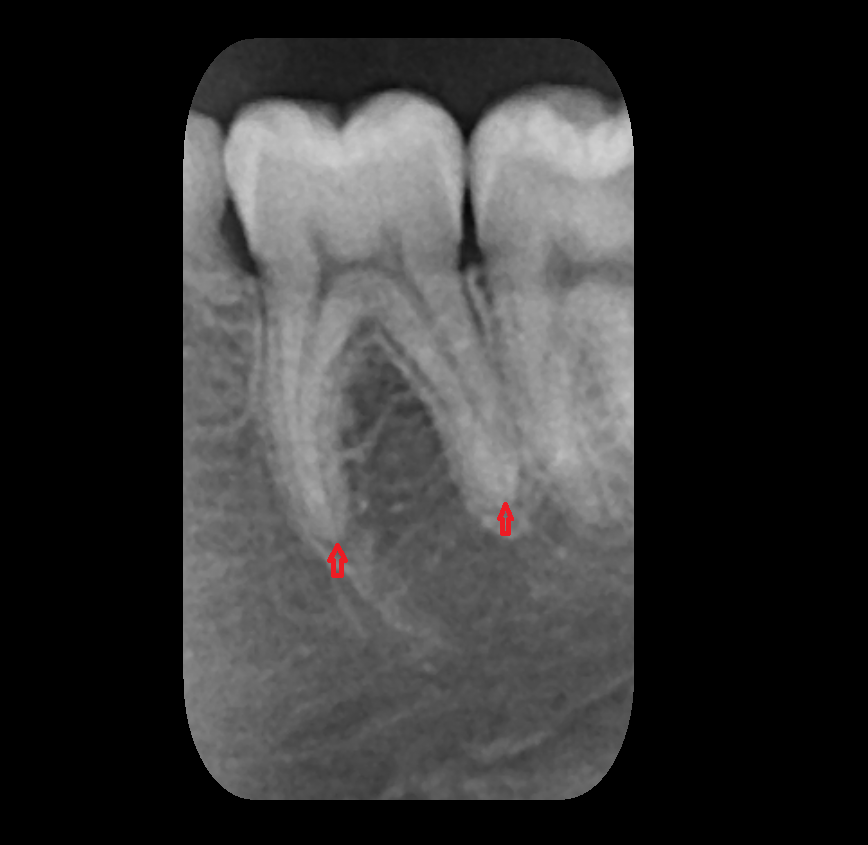

- Root of lower molar tooth

- Lower molar apical foramen

- Upper premolar apical foramen

- Root of upper molar tooth

- Root canal of upper molar tooth

- Dental pulp of upper molar tooth

- Dental pulp of lower molar tooth